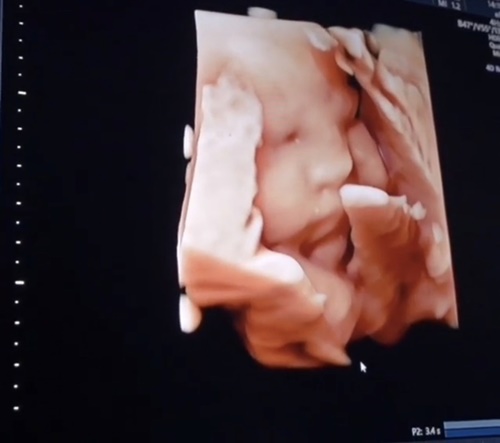

ยิ่งท้องก็ยิ่งสวยจริงๆ สำหรับว่าที่คุณแม่ก้อย วลัยลักษณ์ หรือ ก้อย Saturday Seiko ภรรยาสุดที่รักของ โย่ง อาร์มแชร์ และเรียกว่าใกล้เข้ามาทุกทีที่ทั้งคู่จะได้เห็นหน้าลูกสาวที่ทางGFC (Genesis Fertility Center) ศูนย์รวมบริการทางการแพทย์สำหรับมีบุตรยากแบบครบวงจร ได้มอบให้เป็นของขวัญที่มีค่าที่สุดในชีวิต ซึ่งตอนนี้ว่าที่ คุณแม่ก้อย กำลังตั้งท้องได้ 32 สัปดาห์แล้ว และก่อนที่จะคลอด ว่าที่คุณพ่อโย่ง ก็ได้โชว์ภาพอัลตราซาวด์ลูกสาวล่าสุด ซึ่งภาพนั้นชัดมากจมูกโด่งสันเป็นคม แก้มยุ้ยมากลูก งานนี้บอกเลยว่าฉายแววสวยเหมือนแม่ตั้งแต่อยู่ในท้องจริงๆ

ซึ่ง พ่อโย่ง ได้เขียนแคปชั่นบรรยายไว้ว่า @yongarmchair วันนี้คนสวยของพ่อโย่ง โชว์แก้มยุ้ยฉลองอายุครบ 32 สัปดาห์ 6 วัน แถมยังแอบลืมตาส่งยิ้มหวานให้คุณพ่อคุณแม่ด้วย รักหนูที่สุดเลยนะครับ ใกล้จะเจอกันแล้วน้าาา #โย่งน้อยก้อยจูเนียร์ #yongkoifamily